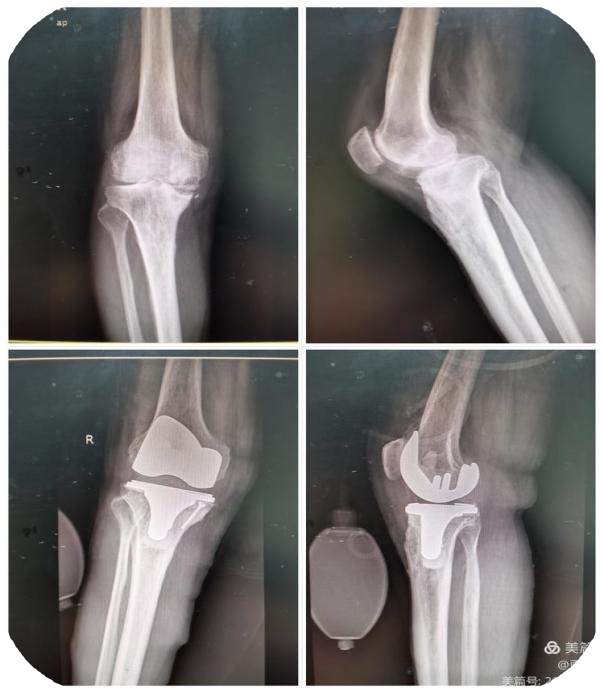

玉林市中西医结合骨科医院创伤二科特长创伤骨折脱位的中西结合治疗,普通手术或微创手术,包括各种关节置换治疗、腰椎疾患、骨质疏松症治疗等。熟练应用快速复位骨折牵引床、G臂、C臂及人工智能机器协助手术。科室有多种物理治疗仪,开展中医中药艾灸治疗等。对指导患者术后快速康复有丰富的临床经验。现有医护人员21名,副高主任医师有1名,主治医生6名。护理人员14名,其中主管护士有3名、护师有2名、护士有9名。